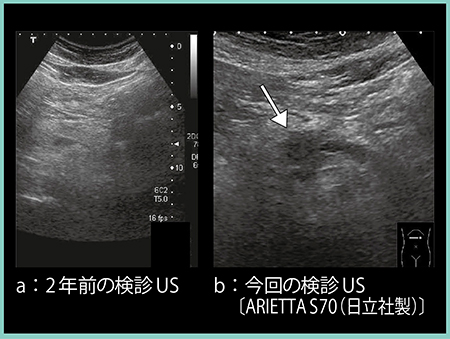

症例3は,62歳,男性。2年前の検診では異常なしであったが(図5 a),検診の超音波検査で膵体部主膵管の拡張と腫瘤を認めた(図5 b↓)。CTでは同部位は造影不良の低吸収域を認め(図6 a↑),MRCPにて体部膵管の狭窄と尾側膵管の拡張を認めたため(図6 b),外科的切除を行った。病理学的には浸潤性膵癌で,T1N1M0,ステージⅡBであった。

図5 症例3:検診発見膵癌の超音波画像